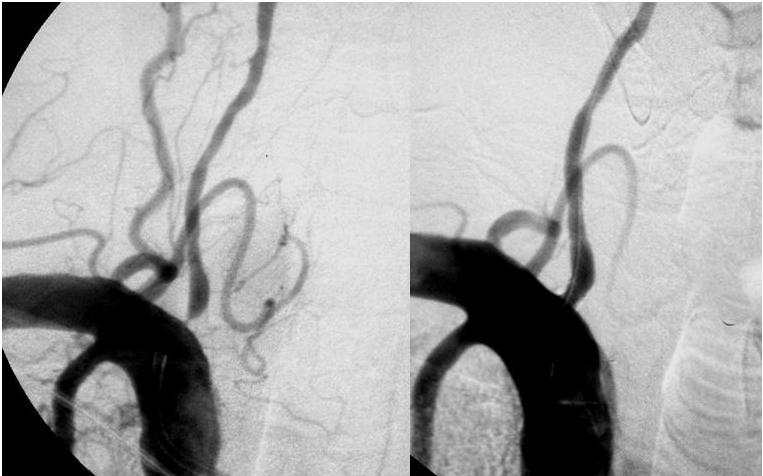

En pacientes con estenosis sintomáticas en el territorio vertebral el tratamiento con stents no fue superior al manejo médico óptimo. Neurology, 19 de septiembre de 2017